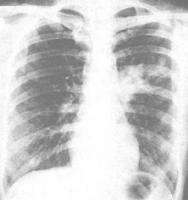

支原體肺炎患者胸部X線檢查變化很大,病變可很輕微,也可很廣泛。體徵輕微而胸片陰影顯著,是本病特徵之一。血常規檢查白細胞高低不一,大多正常,有時偏高。

支原體肺炎的臨床表現和胸部X線檢查並不具特徵性,單憑臨床表現和胸部X線檢查無法做出診斷。若要明確診斷,需要進行病原體的檢測。目前,國內支原體肺炎的診斷主要依靠血清學檢測。